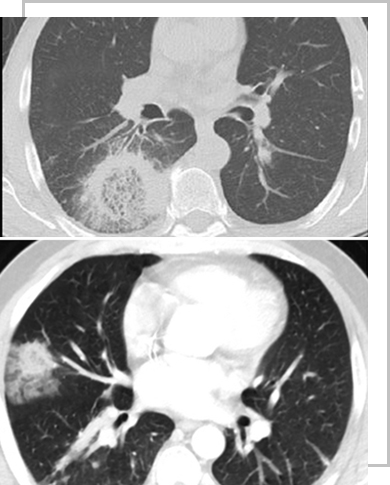

Aspergillus

Mucor